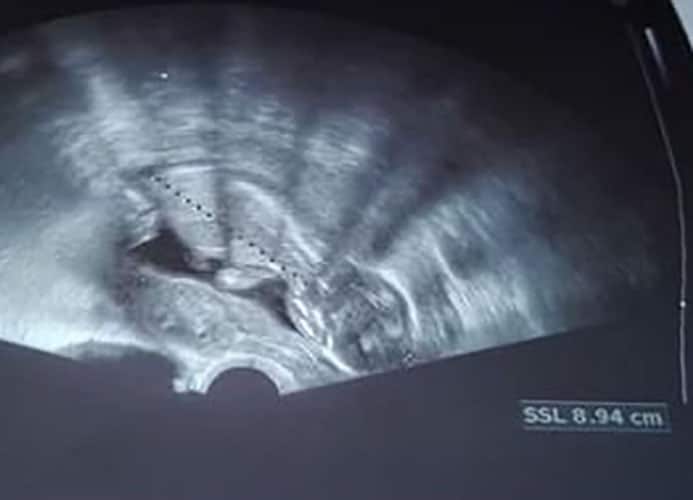

Ultraschallbilder aus dem 2. Trimester (13. bis 28. SSW)

Im 2. Trimester bekommt man oft die schönsten „Ganz-Körper“ Ultraschallbilder. Das Baby ist nun so groß, dass man alles gut erkennen kann und noch nicht zu groß, so dass es noch ganz auf das Bild passt. In dieser Zeit lässt sich meist das Geschlecht bestimmen, wobei manche Babys es einfach nicht preis geben wollen und sich immer so drehen, dass man nichts erkennen kann.